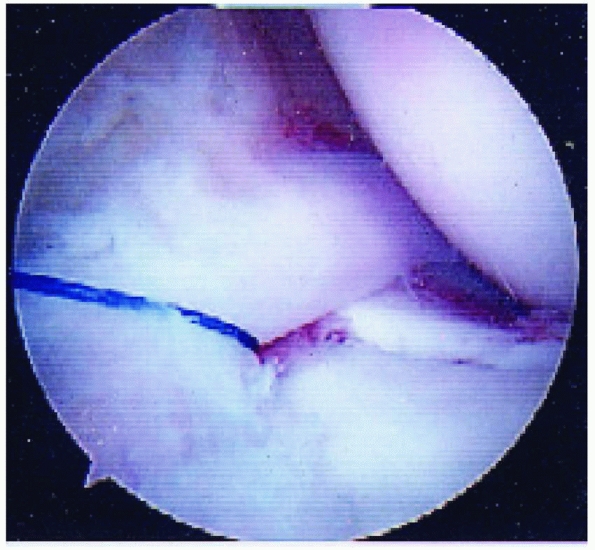

displaced (type 3) fractures. The entrapped meniscus can typically be

extracted with an arthroscopic probe and retracted with a retaining

suture (Fig. 24-6).

FIGURE 24-6 Retraction of an entrapped anterior horn medial meniscus using a retaining suture.